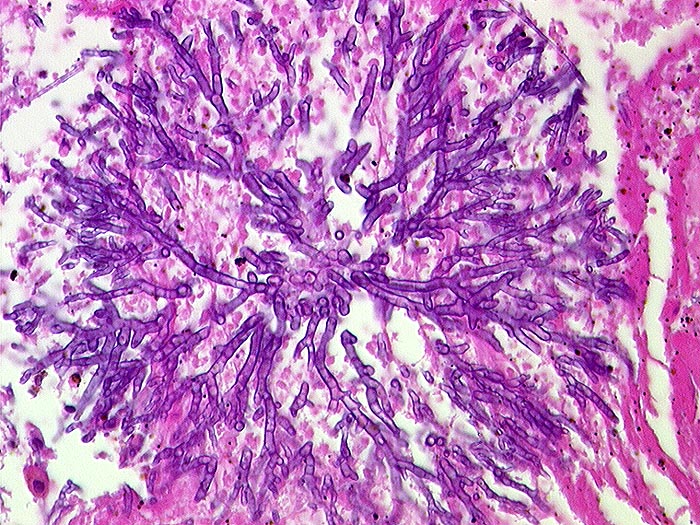

PathoPic ID 547 - Aspergillose

Aspergillose

Spitzwinklig verzweigte septierte Hyphen.

Histologie